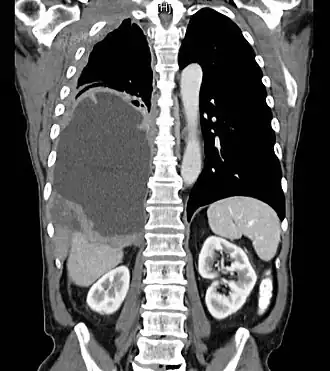

| Grande mesotelioma ao redor do pulmão direito (lado esquerdo da imagem) | |